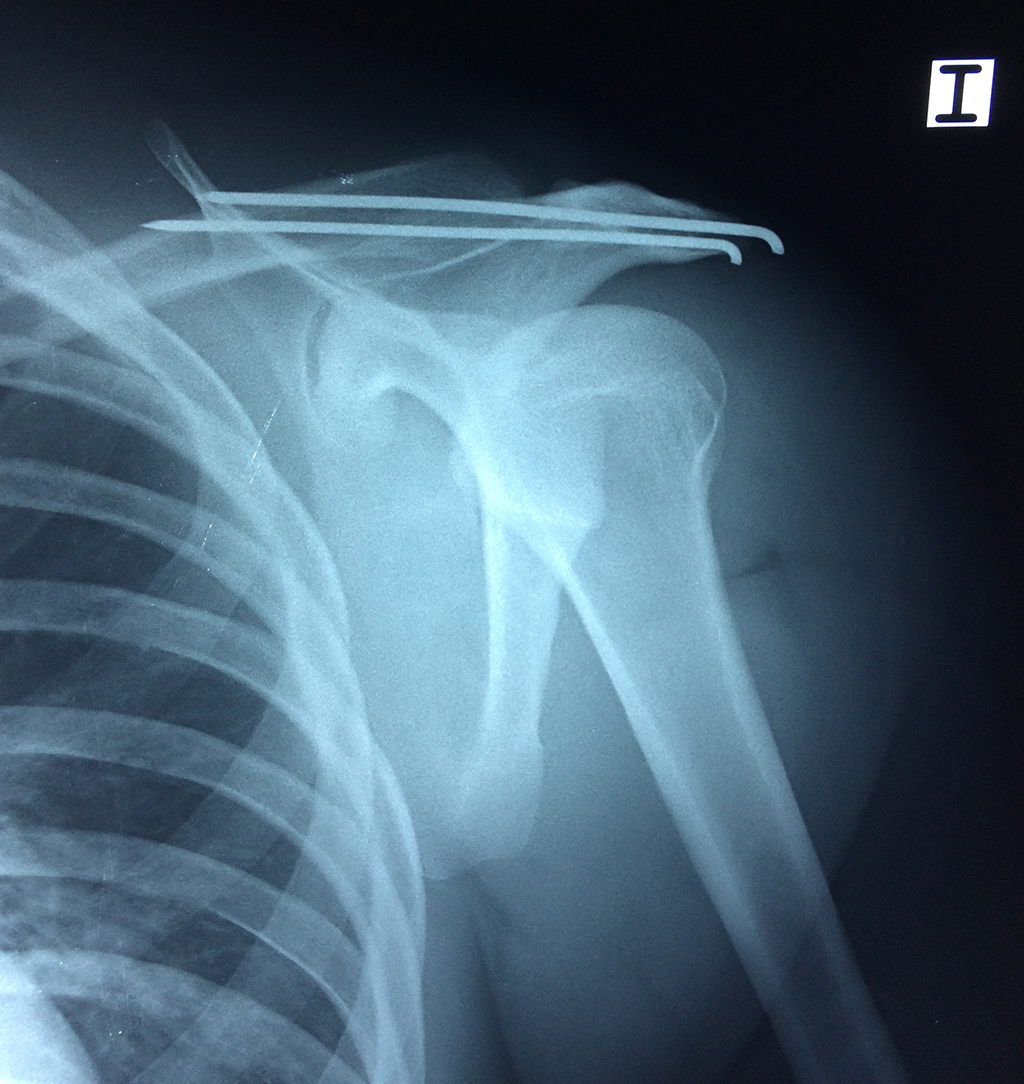

La principal articulación del hombro es la que une la cabeza del húmero con la escápula, recibe el nombre de articulación escapulohumeral y presenta dos superficies articulares, una de ellas corresponde a la cabeza del humero que tiene forma semiesférica y la otra es la cavidad glenoidea de la escápula, estas superficies están recubiertos por cartílago que permiten un movimiento suave e indoloro.